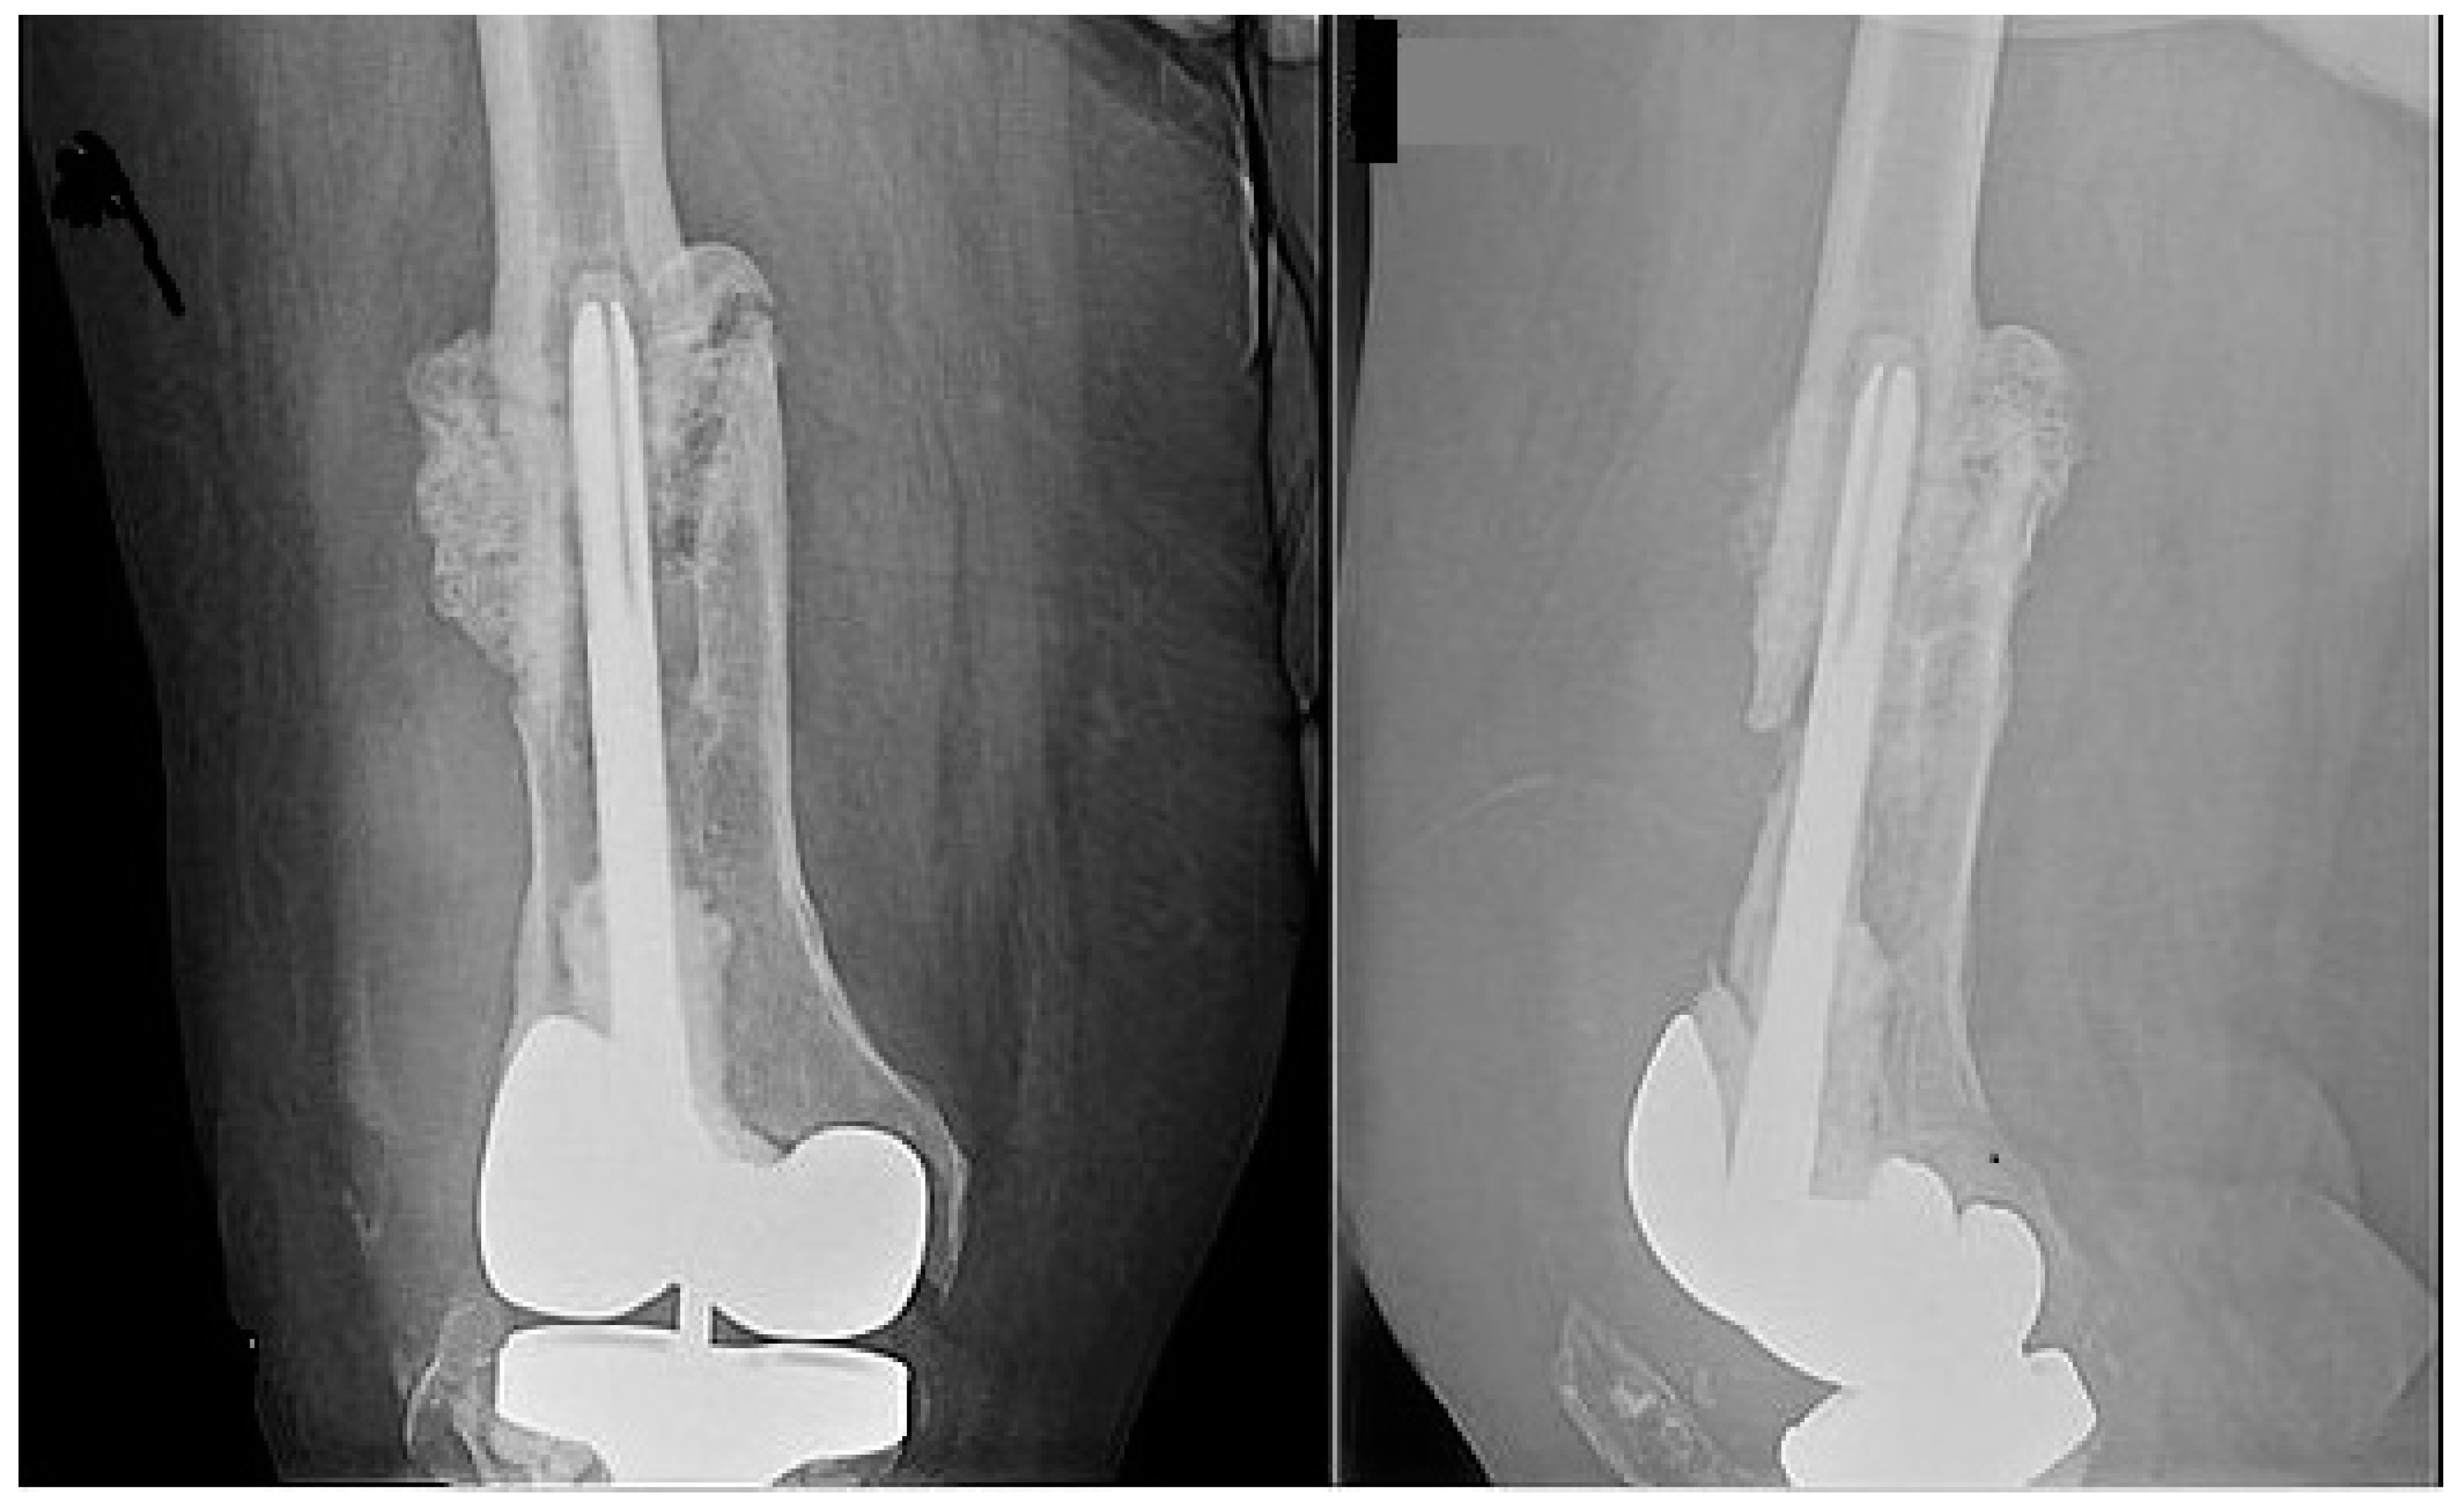

1. Introduction

2. Case